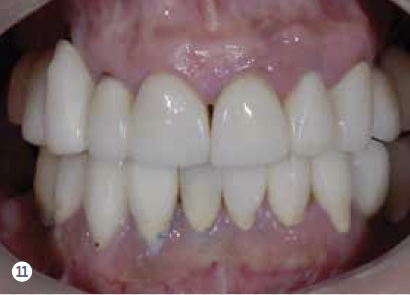

After evaluating the contingency, priority, and risk, a clinician can determine the prognosis. Because every patient presents with different risks, priorities, and contingency factors, a standard treatment plan will not work for every patient. Therefore, a customized treatment plan is necessary to develop a plan based on the patient’s CPR. For example, utilizing the CPR protocol, a segmented reconstruction can be planned for a patient—if appropriate—that consists of an implant-supported screw-retained restoration (Figure 10 through Figure 15). By combining these three assessment tools, clinicians are able to create better solutions and treatment plans for their patients.

Fig 11. Clinical retracted view of the reconstruction. Notice the uneven gingival margins and the ill-fitting restorations.

Figure 11